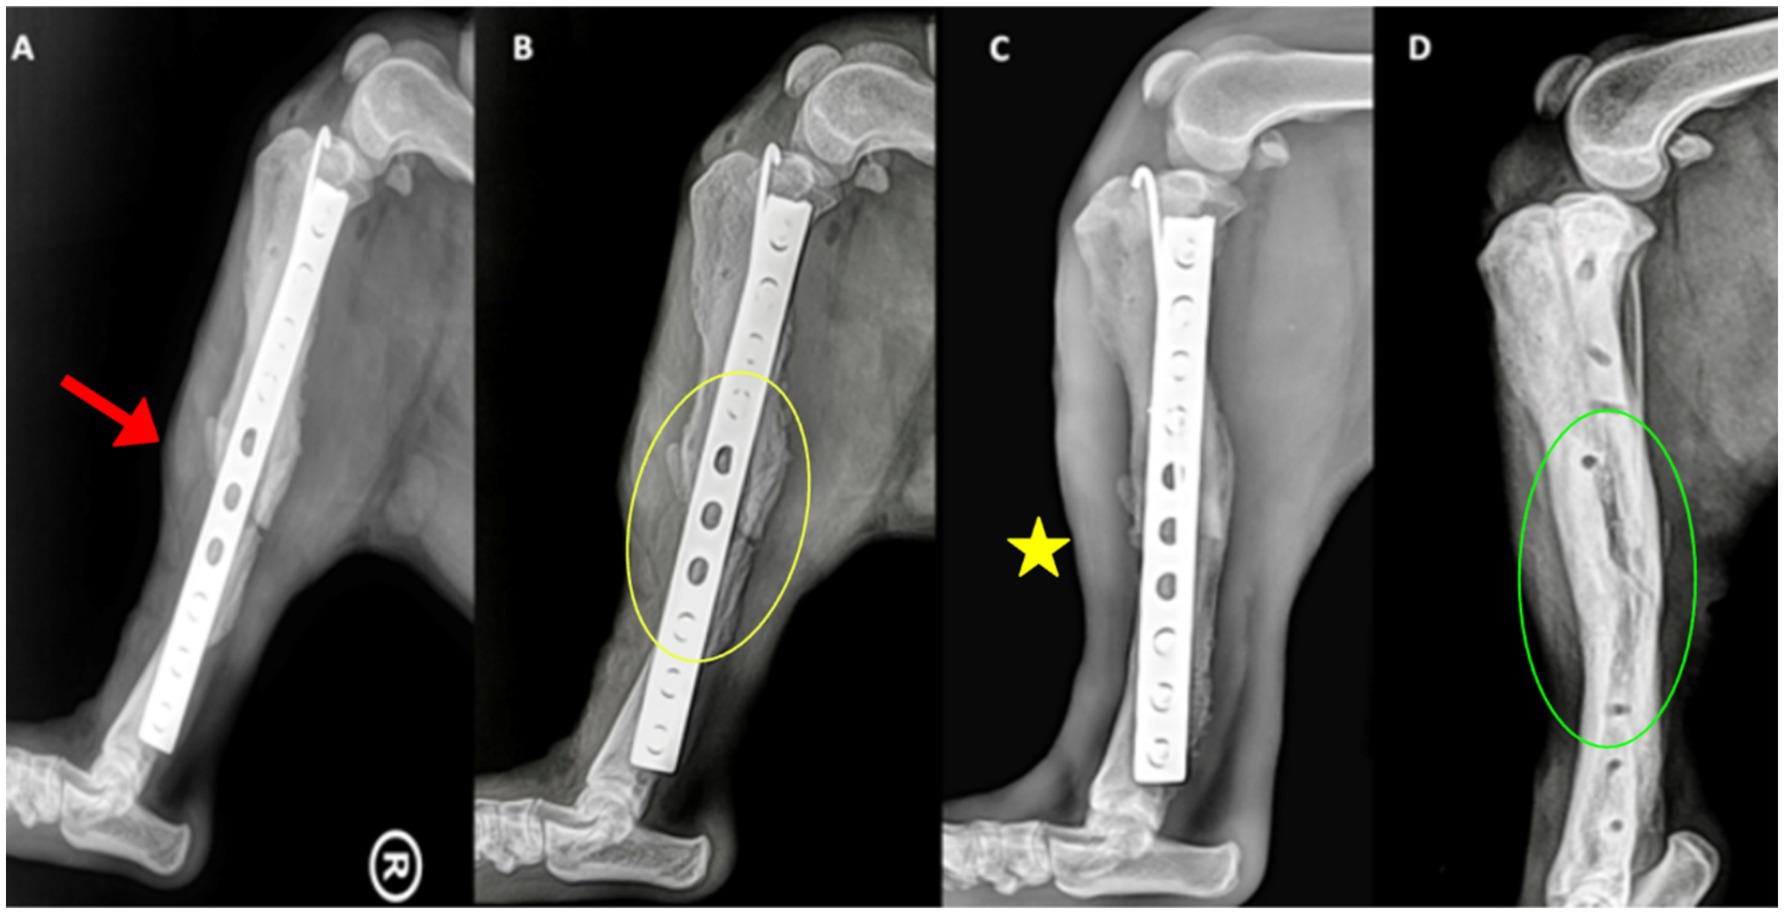

Radiographs at day 0 confirmed correct implant placement and alignment (Figures 3A, 4A). At 8 weeks, bone callus formation and progressive gap closure were evident, without excessive reaction or osteolysis (Figures 3B, 4B). By week 12, the fracture site was fully bridged by a mature callus, with optimal implant positioning and no evidence of osteolysis or inflammation (Figures 3C, 4C). Consequently, implant removal was performed at week 12, with radiographs confirming complete bone healing and restoration of diaphyseal integrity (Figures 3D, 4D).

Figure 4. Mediolateral radiographs of the right tibia. (A) Day 0, showing implant alignment and osteotomy site (red arrowhead). (B) At 8 weeks, callus formation (yellow circle) is evident along the osteotomy margins. (C) At 12 weeks, the callus bridges the fracture site (yellow asterisk), with no evidence of implant loosening or inflammatory reaction. (D) After implant removal, the bone has fully consolidated, with smooth cortical contour restored (green circle).